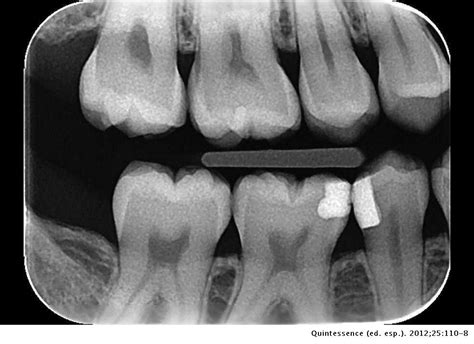

Para poder observar con claridad la tercera raíz son necesarias varias radiografías30,31. La obtención de una sola radiografía puede conducir con facilidad a errores de diagnóstico (fig. 2a). La colocación de una lima en la raíz adicional puede ofrecer el aspecto de una perforación13 (fig. 2b). Cuando los hallazgos radiográficos no son definitivos, la información que aportan los localizadores de ápice electrónicos nos permite hacer un diagnóstico diferencial y confirmar la presencia de conductos adicionales.

Walker y Quackenbush26 llevaron a cabo un estudio y concluyeron que el simple análisis de radiografías de aleta de mordida permitía la detección de las raíces distolinguales en el 90% de los casos (fig. 3).